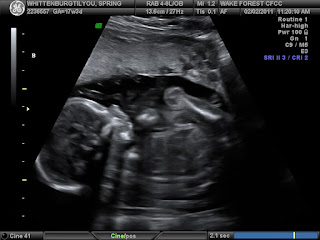

We went yesterday to have the babies checked out, they are all doing great!!! They are growing good. I thought as they got bigger they would be easier to see, but as the tech said and we noticed, they are getting harder to photograph, 1 because they are getting crowded and 2 there are body parts everywhere, lol. Baby A is up to 12 ounces, Baby B is also 12 ounces, and Baby C is 13 ounces. The doctor was very happy with their growth. They have been able to get a look at almost all the organs on each of the babies and they all look good too. It's hard to see some things on Baby C because he is in the middle and the tech can't always get the right angle to see him from all sides, so I think they are still trying to get a better look at him.

Well here are a few photos of the boys... like I said they are getting harder to photograph

| Baby A facing the camera |

| Baby B, I think it's the side of his head, he has a hand above his head and of course his body and leg & knee |

| Baby C, side profile of his pretty little head & body and arm, I'm not sure if that is his leg in front of him or one of his brothers? |